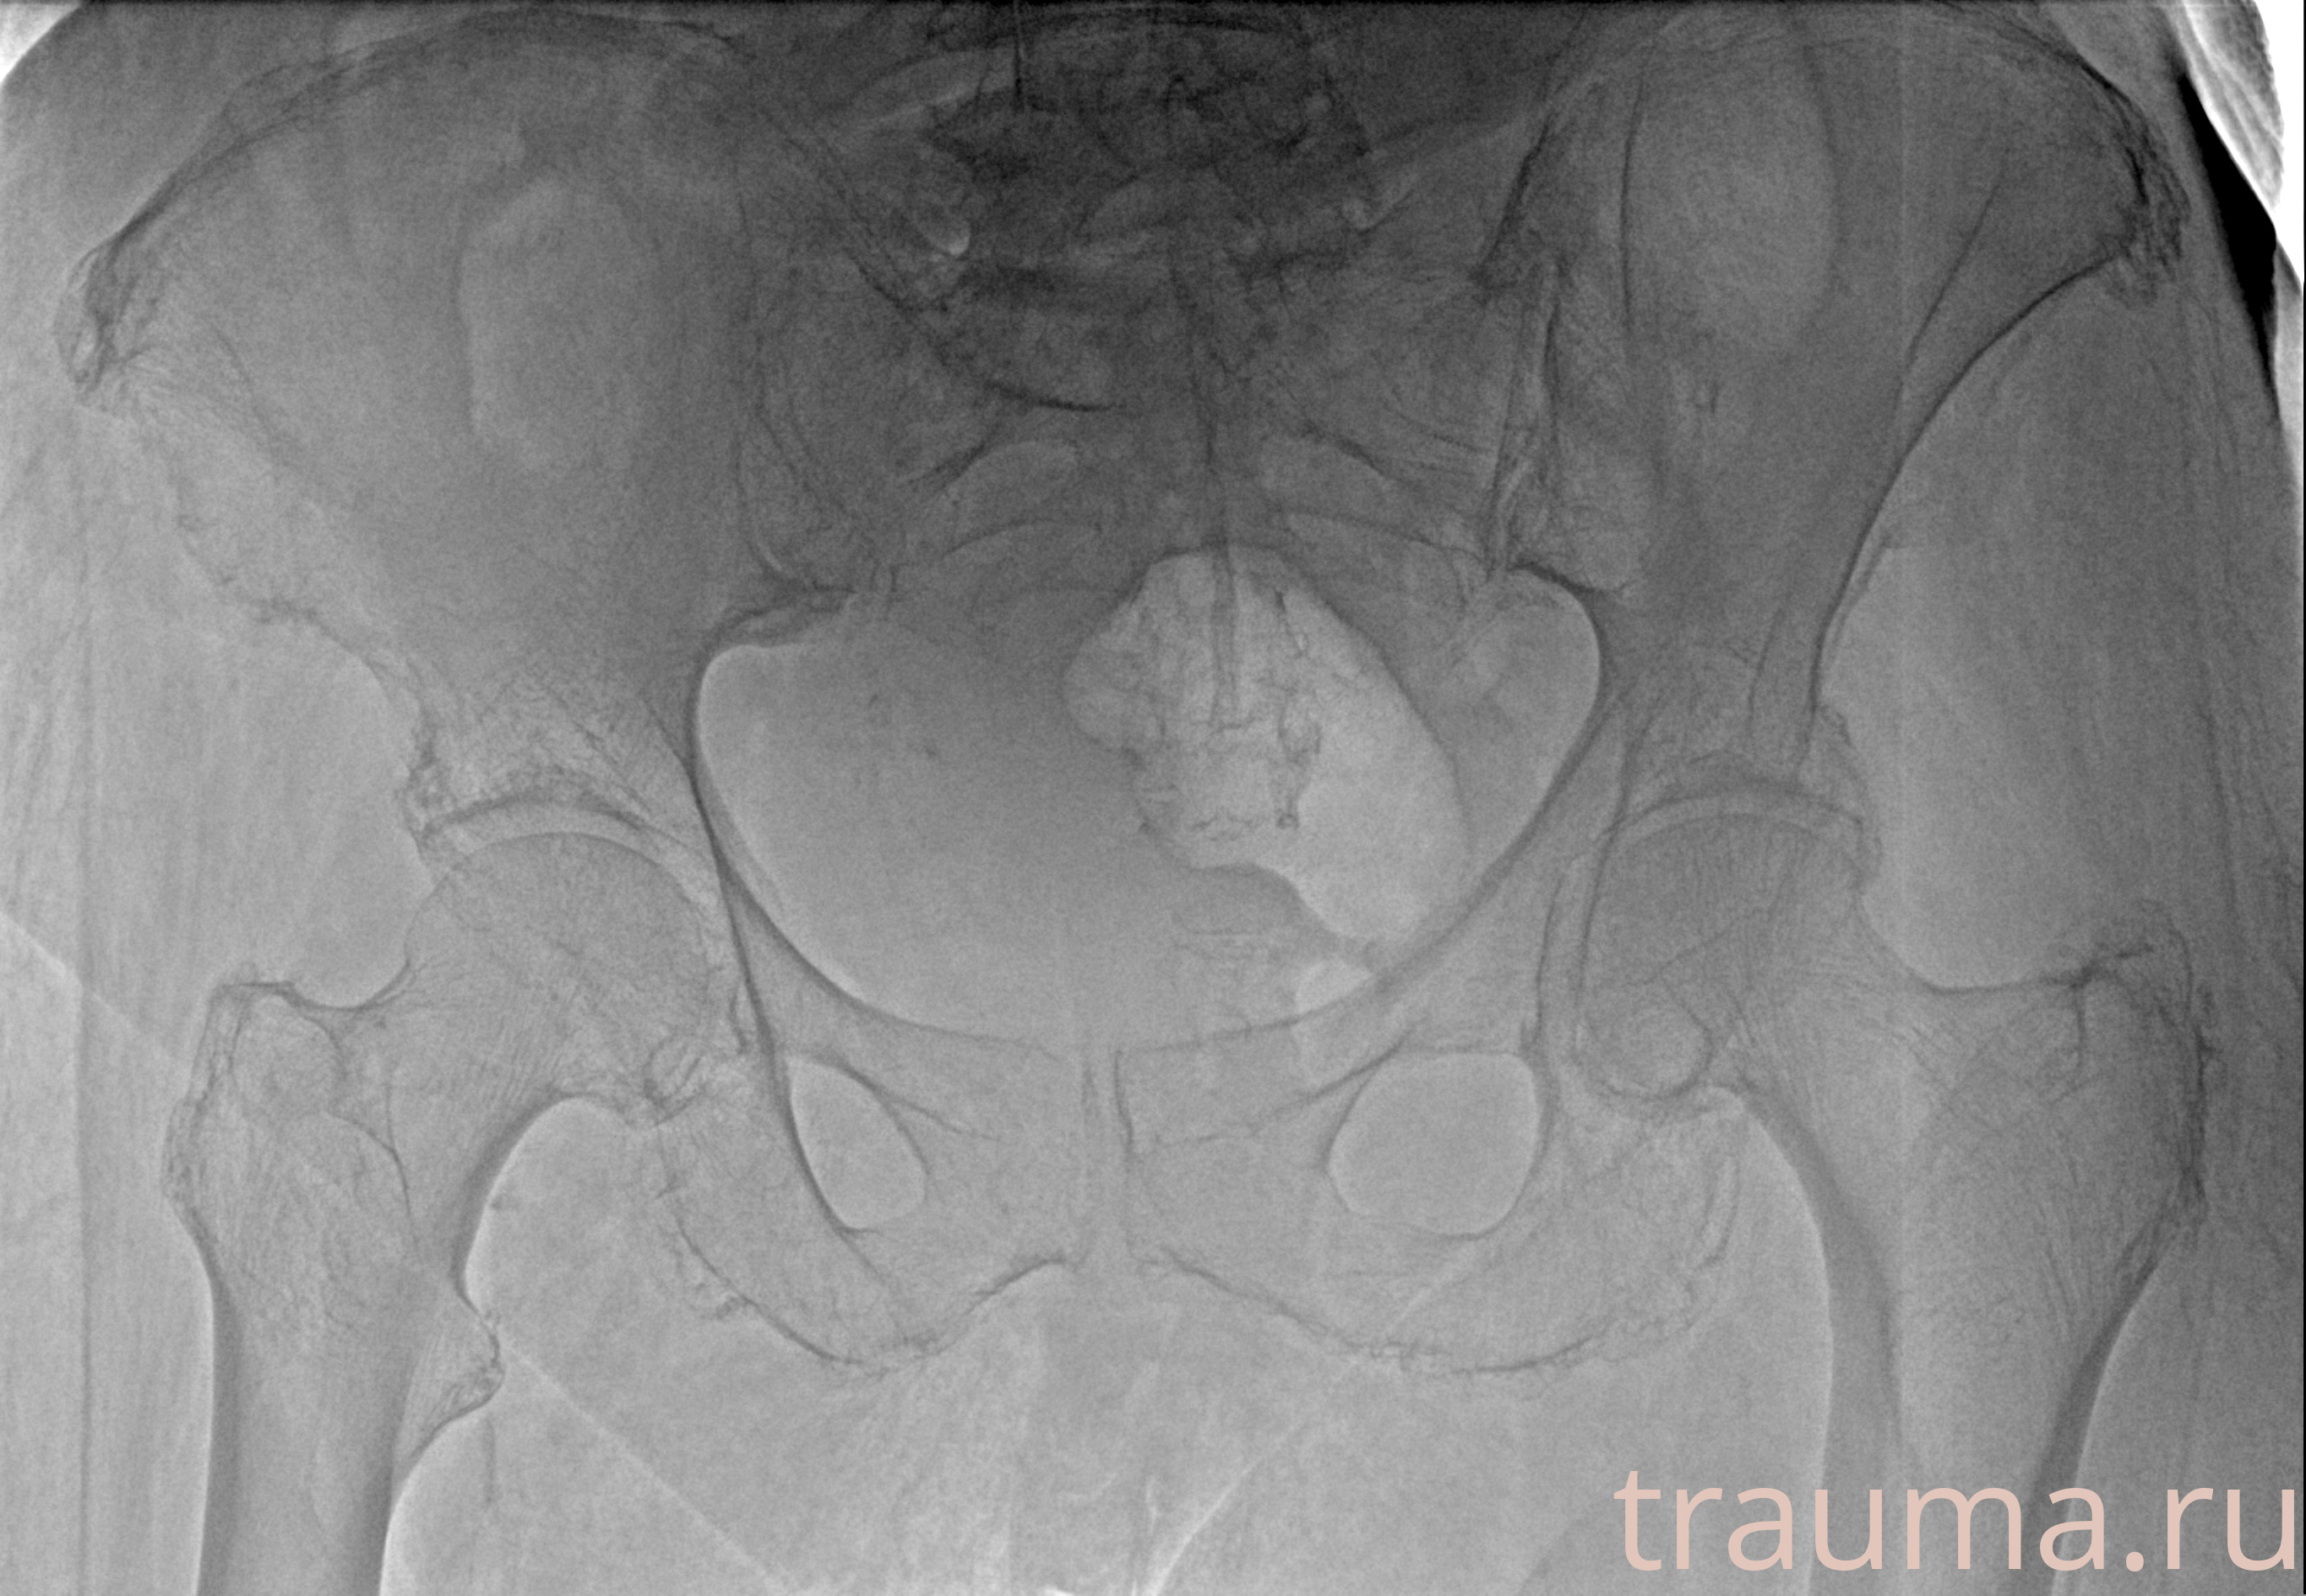

Рентгенограммы

Рентген на дому: по вашему адресу приезжает врач-рентгенолог, травматолог-ортопед с мобильным рентгеновским аппаратом, проводит диагностику травмы или заболевания, делает необходимые рентгенограммы, дает рекомендации по дальнейшему лечению. Получить качественные снимки в домашних условиях возможно благодаря уникальной методике, разработанной МосРентген Центром для института  Склифосовского